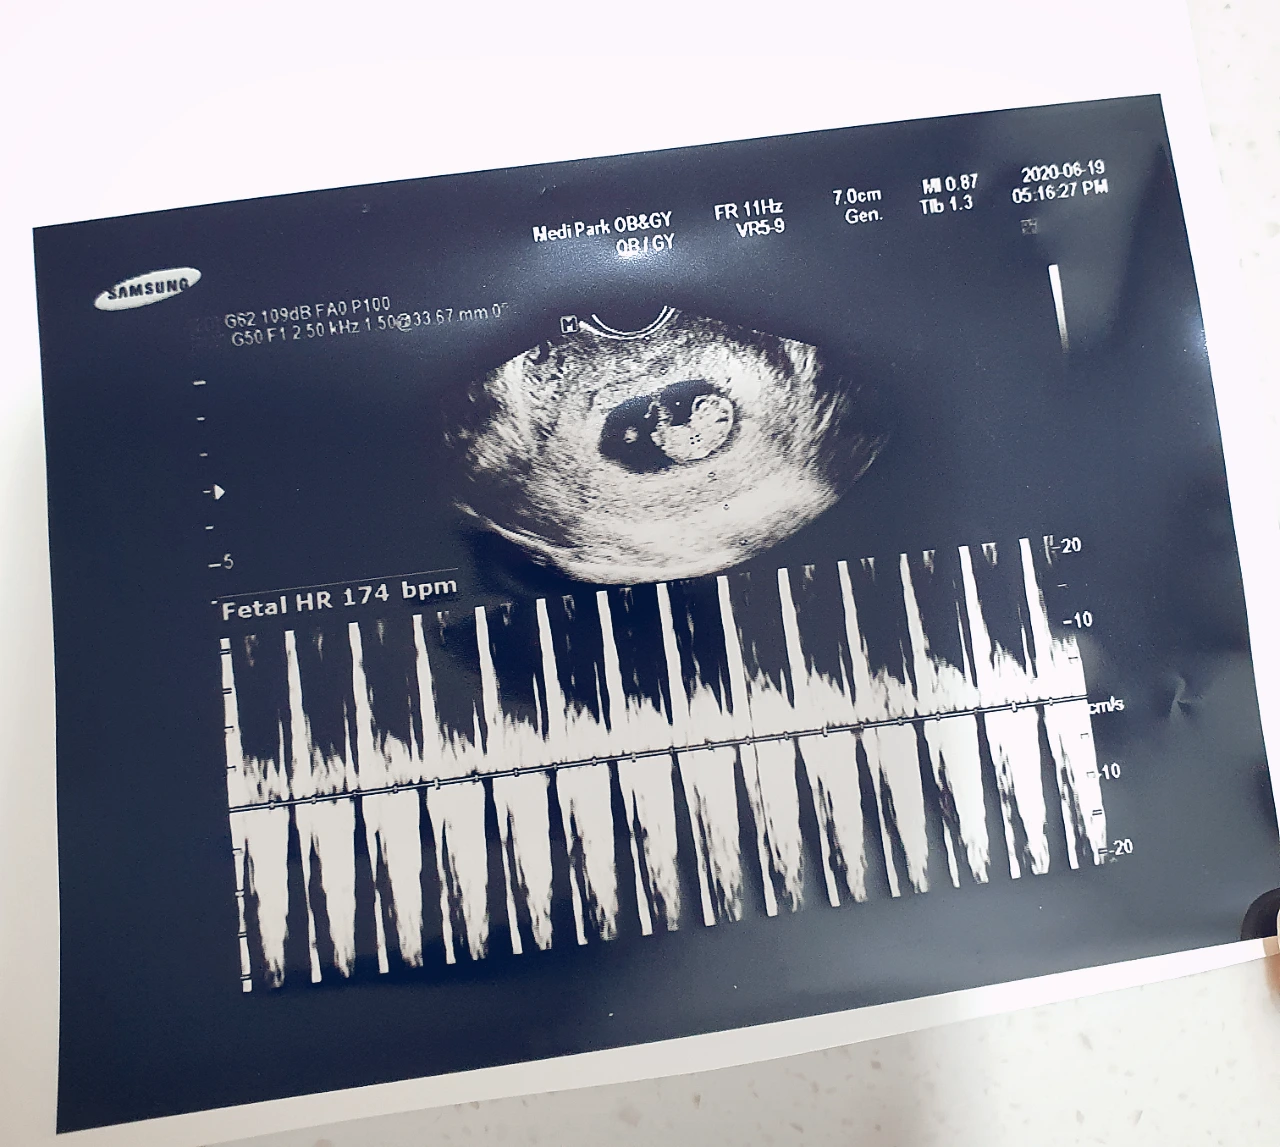

9주차(좌)에서 13주차(우)로 폭풍 성장한 셋째의 초음파 사진